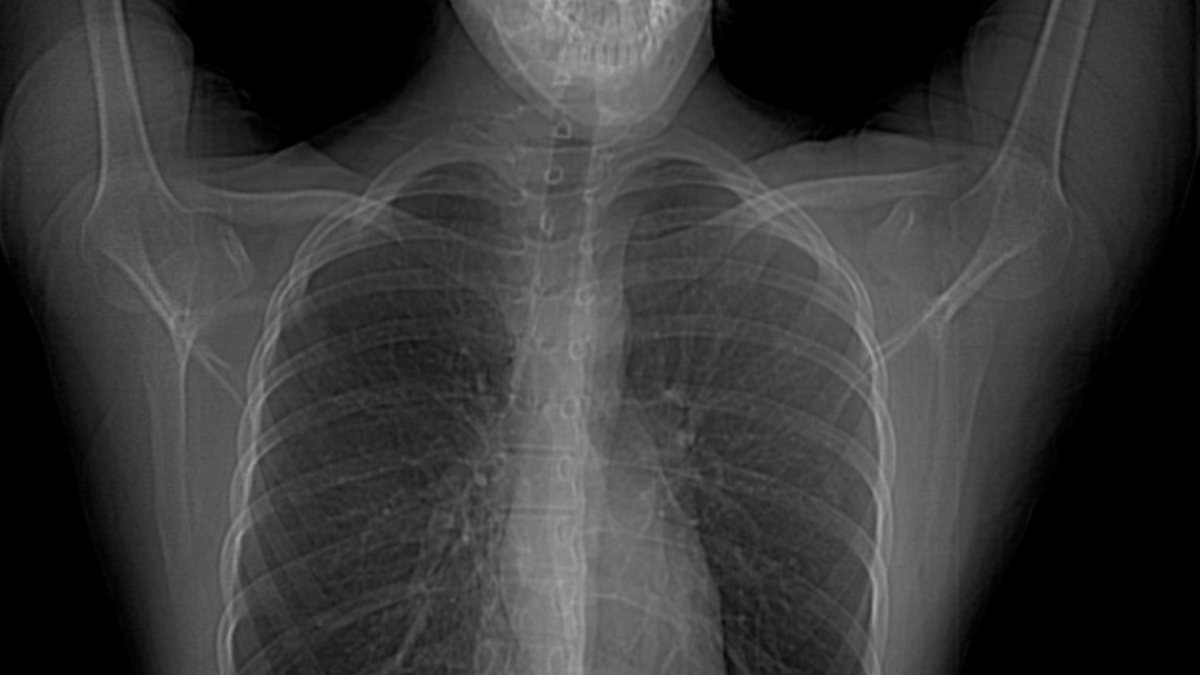

CXR showing chest wall deformity with fusion of the right 4th, 5th and What Is Chest Deformity This can affect heart and lung function. Pectus excavatum (pe), translated literally as “hollowed chest” and also referred to as sunken chest or funnel chest, is the most common chest wall deformity seen in children. Pectus excavatum causes the breastbone to sink into the chest. Home health conditions and diseases. Pectus excavatum causes the breastbone to sink into the chest.. What Is Chest Deformity.